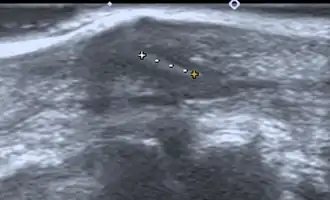

If manual detection and localization fail, the main methods for medical imaging of splinters are:

- Medical ultrasonography – used to locate glass, metal, pencil graphite, some plastics, stone, and some types of wood.[6]

Small wooden splinters (1–4 mm) distant from bones are most easily detected by ultrasonography, while CT scan and magnetic resonance imaging have higher sensitivity for those near bones.[7]